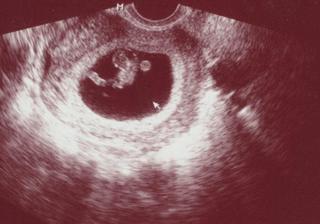

@petinkas no nějaký výsledky z moči mi psala sestřička hned do tý průkazky jestli bílkoviny a ještě něco.. jj tu krev budeme probírat toho 17. ale vychází to na 12+2 on říkal že se ty placený screeningový testy dělaj v 11. týdnu to je ta krev a ve 13 ta šíje 😉 no ale jestli jsi podle UZ 8+1 a já 8+2 a TP mám 29.7. tak to budeš mít o den dýl 😀 to je fakt sranda a neboj nic budeme v pořádku a fazolata taky=) máš ho tam hezky namáčklýho v růžku to my se hezky rozvalujeme 😀

@dashyyy Jeee, krasná fazolečka, moc gratuluju 🙂 to je sranda, jsme na tom skoro stejně, to je super 🙂 kráásný, opatrujte se 🙂 🙂

@petinkas Jee, kráááásný !! moc gratuluju a kolik tam má místa, to ten náš ufonek se tak rozvalovat nemůže 😀 moc krasny, opatrujte se 🙂

Ahojky holky, tak my na kontrole taky super, jsem 8tt+2, měříme 18mm, TP je 29.7. a srdíčko tlouklo úplně nádherně - bylo to úžasné... úplně mi tekly slzy, jak jsem byla dojatá.. 😉 fotečku přidám zítra. Dokonce už mi vypsal i průkazku, tak to máme oficiálně! 🙂 🙂 další kontrola 6.1. to jdu i na krev a moč. a domluvíme screening. 😉 🙂